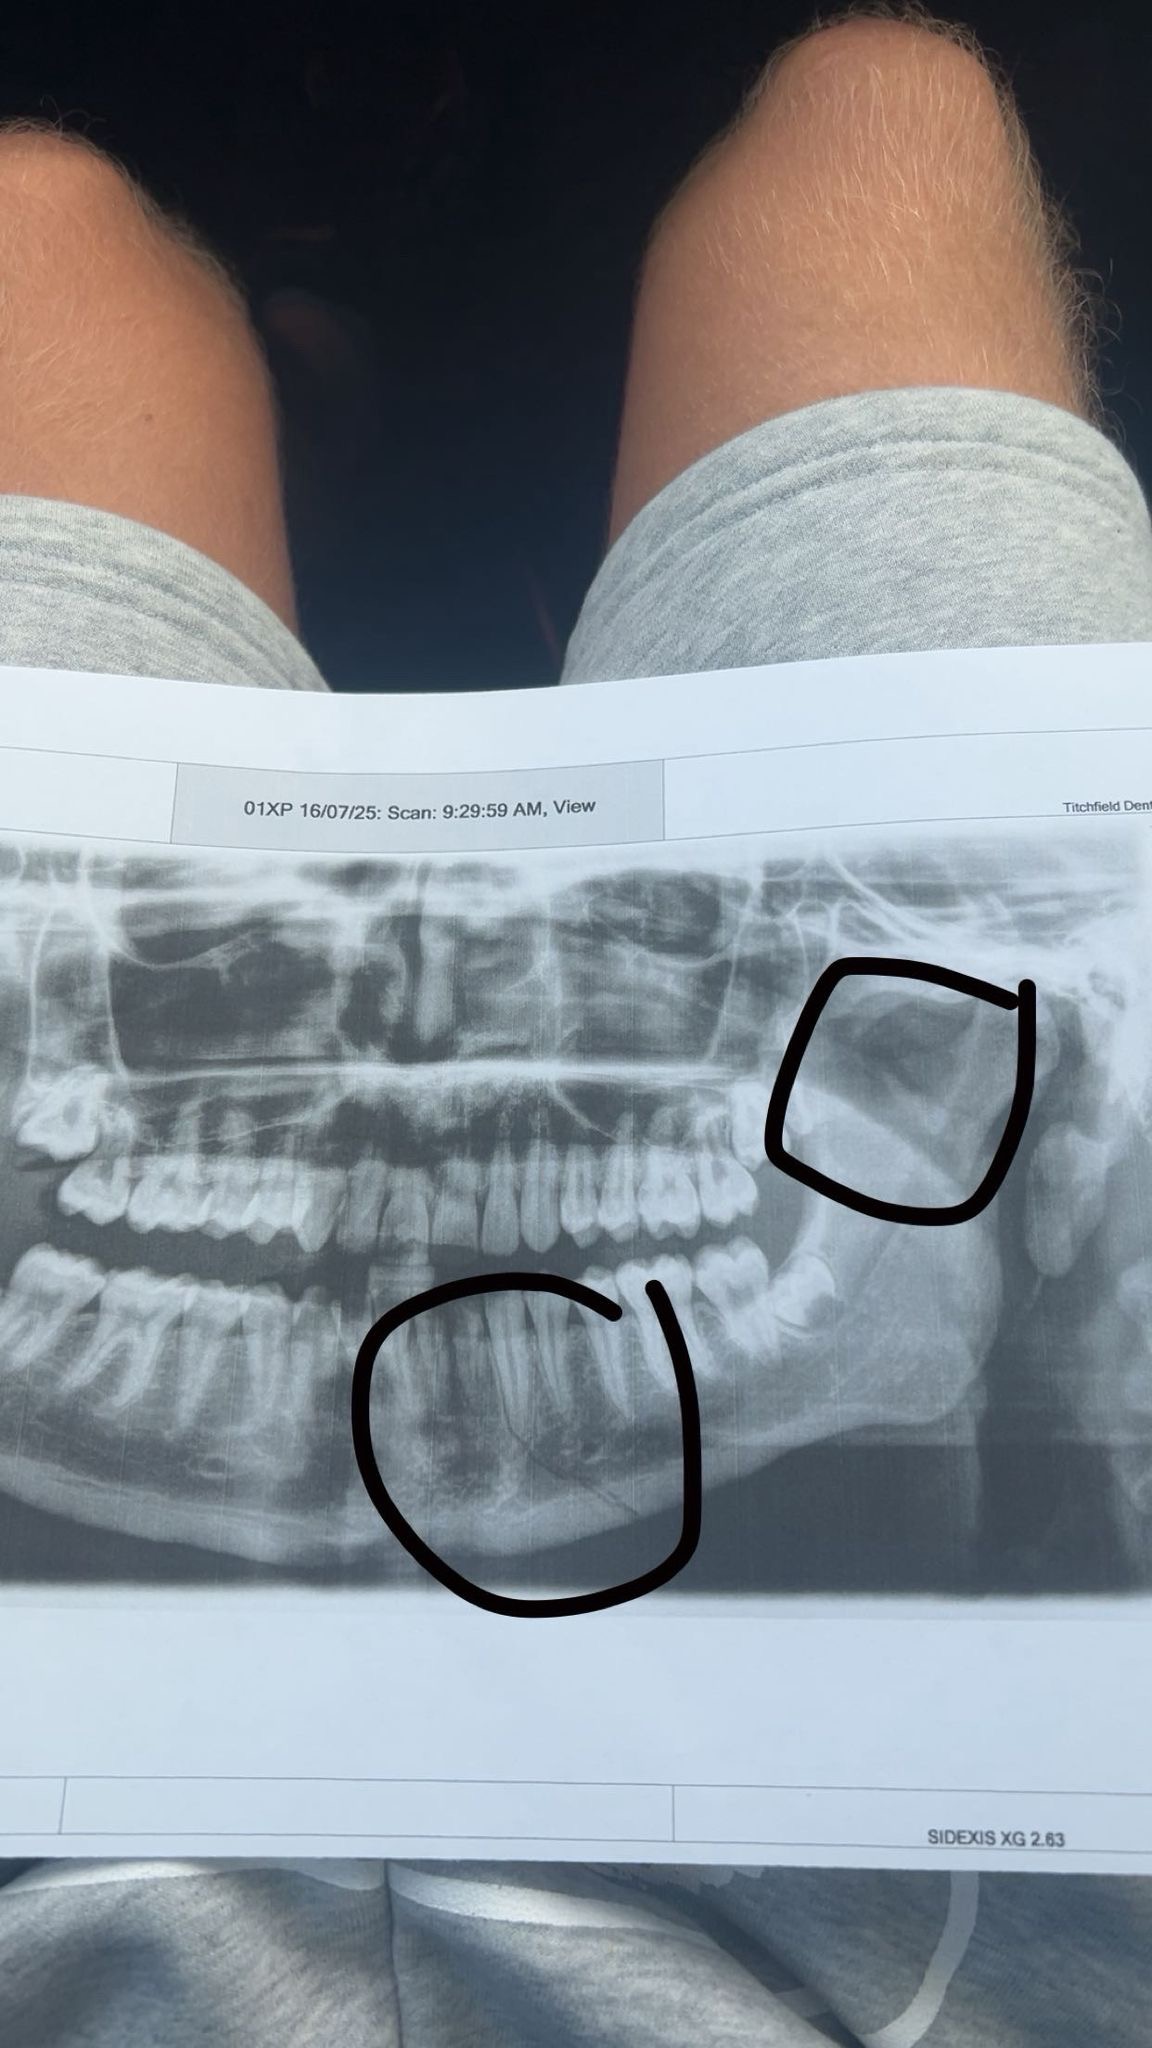

Once home it was revealed that he had been hit so hard that his jaw was fractured in two places and required emergency surgery to have 2 metal plates fitted in his jaw.

Jonny is recovering well from the operation but he still suffers daily with pain and discomfort and eating is difficult. He has a big scar that constantly reminds him of what happened and he faces likelihood of having long term problems later in life.